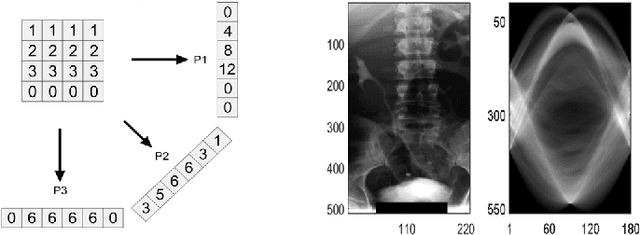

Radon transform and its inverse operation are important techniques in medical imaging tasks. Recently, there has been renewed interest in Radon transform for applications such as content-based medical image retrieval. However, all studies so far have used Radon transform as a global or quasi-global image descriptor by extracting projections of the whole image or large sub-images. This paper attempts to show that the dense sampling to generate the histogram of local Radon projections has a much higher discrimination capability than the global one. In this paper, we introduce Local Radon Descriptor (LRD) and apply it to the IRMA dataset, which contains 14,410 x-ray images as well as to the INRIA Holidays dataset with 1,990 images. Our results show significant improvement in retrieval performance by using LRD versus its global version. We also demonstrate that LRD can deliver results comparable to well-established descriptors like LBP and HOG.